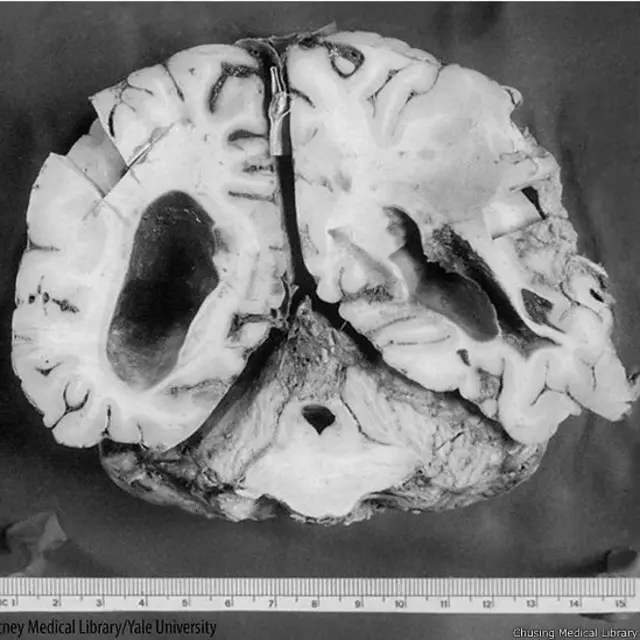

El médico Harvey Cushing es considerado el padre de la neurocirugía. Y su colección de cerebros y fotografías de pacientes fue clave en el desarrollo de esta especialidad.

Más de 10.000 imágenes en blanco y negro que fueron digitalizadas recientemente y colgadas en internet por el Centro Cushing de la Escuela de Medicina de la Universidad de Yale.

Y añadió que a pesar de lo impactante de las fotografías, éstas ayudaron al entrenamiento de otros doctores y al desarrollo de la neurociencia.

"Estas imágenes fueron fundamentales en el entrenamiento de otros doctores para reconocer alguna de las enfermedades que ellos necesitaban tratar", afirmó Mr. Chandler.